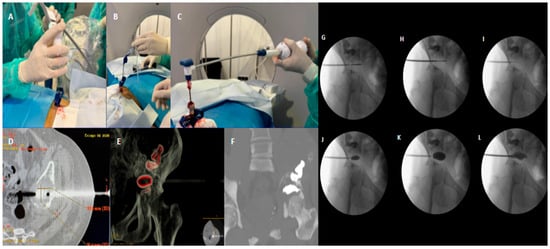

The management of severely comminuted acetabular posterior wall fractures in young, active patients presents a significant surgical challenge. When anatomical open reduction and internal fixation (ORIF) is not feasible, primary total hip arthroplasty (THA) is often considered but is a suboptimal solution due to concerns over long-term implant survivorship and the inevitability of revision surgery. This single-patient technical note presents a novel joint-preserving technique for managing unreconstructible acetabular posterior wall fractures using with cement-augmented screw fixation via the Kocher–Langenbeck approach. A 28-year-old male sustained a left posterior hip dislocation with a comminuted acetabular posterior wall fracture involving >30% of the articular surface, alongside a tibial shaft fracture, following a high-energy motorcycle collision. Intraoperative assessment confirmed the posterior wall was unreconstructible, with six non-viable osteochondral fragments. A joint-preserving salvage procedure was performed. After debridement, a stable metallic framework was created using three screws anchored in the posterior column. Polymethylmethacrylate (PMMA) bone cement was then applied over this framework in its doughy phase, meticulously contoured to reconstruct the articular surface. The hip was reduced, and the tibia was fixed with an intramedullary nail. The patient was mobilized with weight-bearing as tolerated on postoperative day 3. At the 21-month follow-up, the patient reported no pain during daily activities and only mild discomfort during deep squatting. Radiographic and CT evaluations demonstrated a stable hip joint, concentric reduction, well-maintained joint space, and no evidence of implant loosening or osteolysis. Level of Evidence: V (Technical Note/single-patient Case report). For unreconstructible, comminuted fractures of the non-weight-bearing portion of the acetabular posterior wall in young patients, cement-augmented screw fixation offers a viable joint-preserving alternative to primary THA. This technique provides immediate stability, facilitates early mobilization, and preserves bone stock. While long-term outcomes require further study, this case demonstrates excellent functional and radiographic results at 21 months, presenting a promising new option for managing these complex injuries. Full article

Show Figures

Figure 1